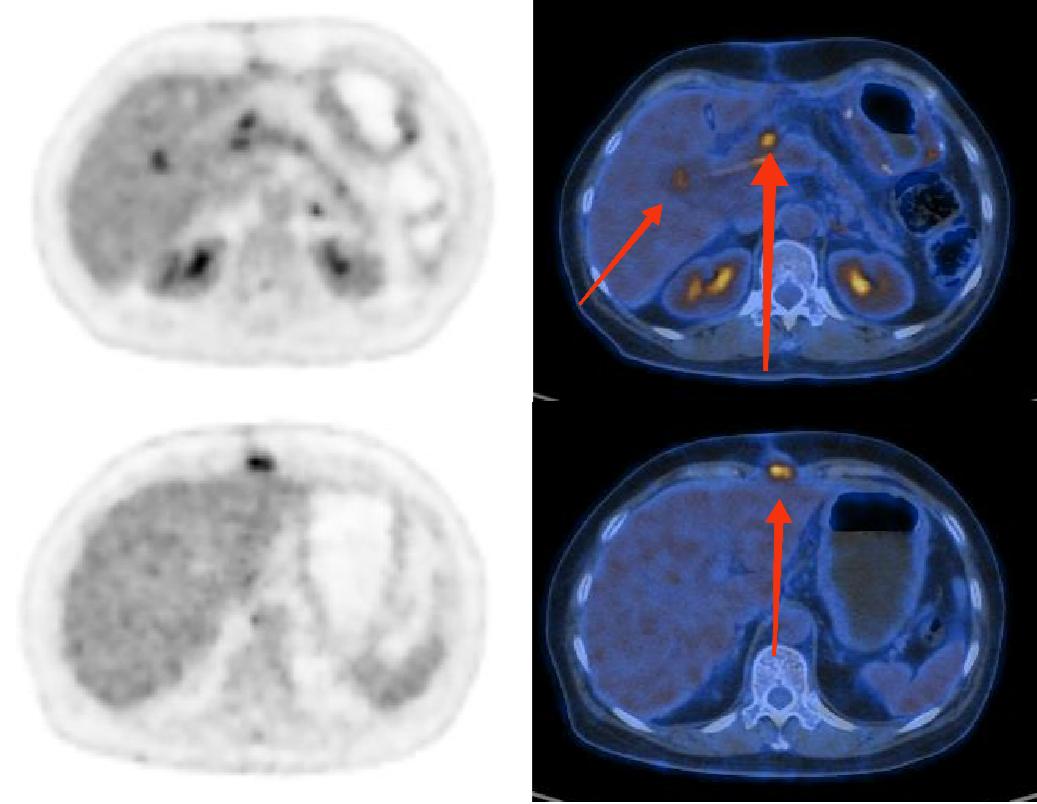

图为18F-FDG PET及PETCT图像。上图两枚红箭头所指为胰十二指肠切除术后吻合口处高代谢病灶,不能完全排除是否为肿瘤术后复发病灶;下图红箭头所指为切口皮下高代谢软组织灶,不能完全排除是否为肿瘤转移灶。

PET/CT作为作为分子影像诊断的“先锋”,可以通过核素标记特殊的“分子探针”显像剂,来显示全身各处的病灶。18F-FDG PET/CT是非特异肿瘤的显像方法,适用于所有肿瘤(包括NEN),但18F-FDG对于神经内分泌肿瘤的诊断价值有限,病灶摄取18F-FDG的程度与Ki-67指数(一种病理标记物)相关,而奥曲肽对于神经内分泌肿瘤的特异性非常高,如果将神经内分泌肿瘤比较为“锁”,那么奥曲肽就是专门打开这把锁的“钥匙”,可以明确内分泌肿瘤是否存在多发、判别复发及隐匿性微小神经内分泌肿瘤。临床上,通常将18F-FDG PET/CT与奥曲肽PET/CT双核素显像联合应用,互相补充以全面评估神经内分泌肿瘤。

我院PET影像中心进行的第一例18F-奥曲肽PET/CT显像应用于一名55岁的女性患者,一个多月前因胰腺内分泌肿瘤进行了胰十二指肠切除术,现继续就诊于湖南省人民医院肿瘤科,临床医生为了明确病情,为其申请了18F-奥曲肽PET/CT显像,期望能更好地给予患者个性化治疗方案。在PET影像中心毛志群主任的带领下,PET影像中心的医护人员全心全意为患者服务,并成功帮助患者及临床医生完善了诊疗方案。